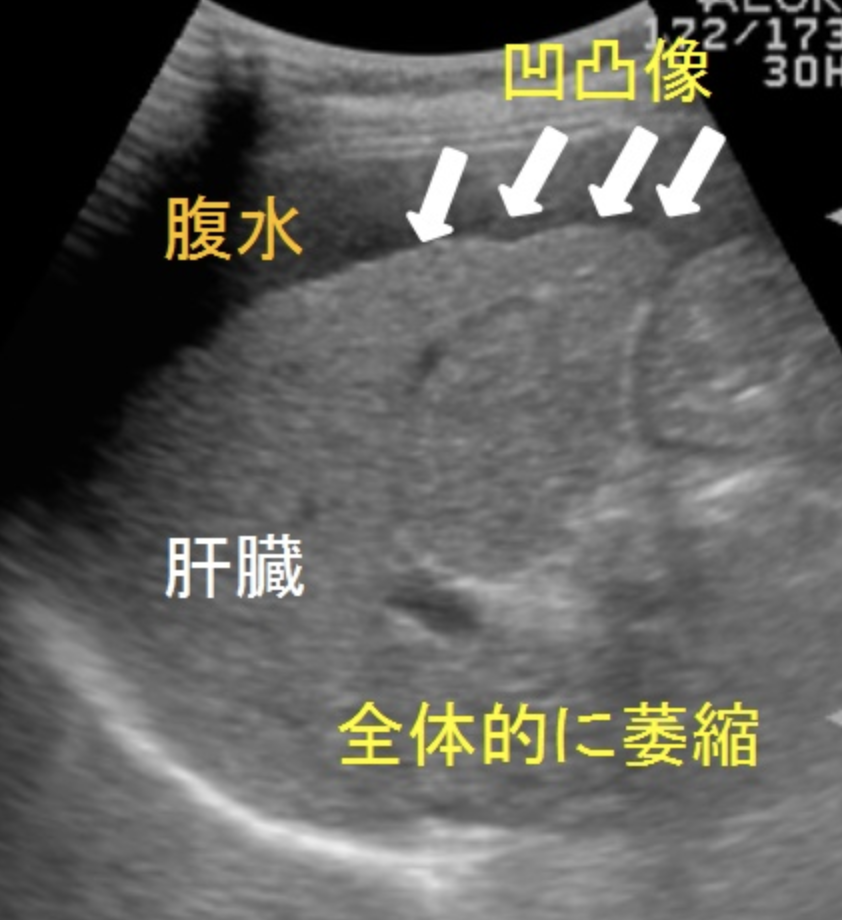

◯肝表面の評価

肝硬変では肝表面に多数の小結節が出現し、肝表面は凸凹不整になる。超音波では肝前面の凸凹は観察しにくいので、肝下面に注目したほうがわかりやすい。